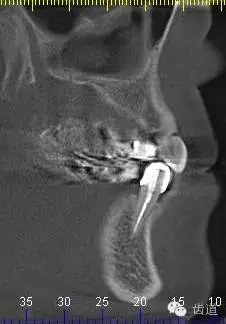

9、34CBCT

10、 26,27CBCT

7、45,46,47CBCT